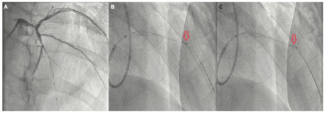

Intravascular lithotripsy (IVL) has been recently approved for calcified coronary lesions. The most striking aspect of using IVL is its ease of use and safety. The serial Disrupt CAD trials evaluated the utility of IVL for lesion preparation...